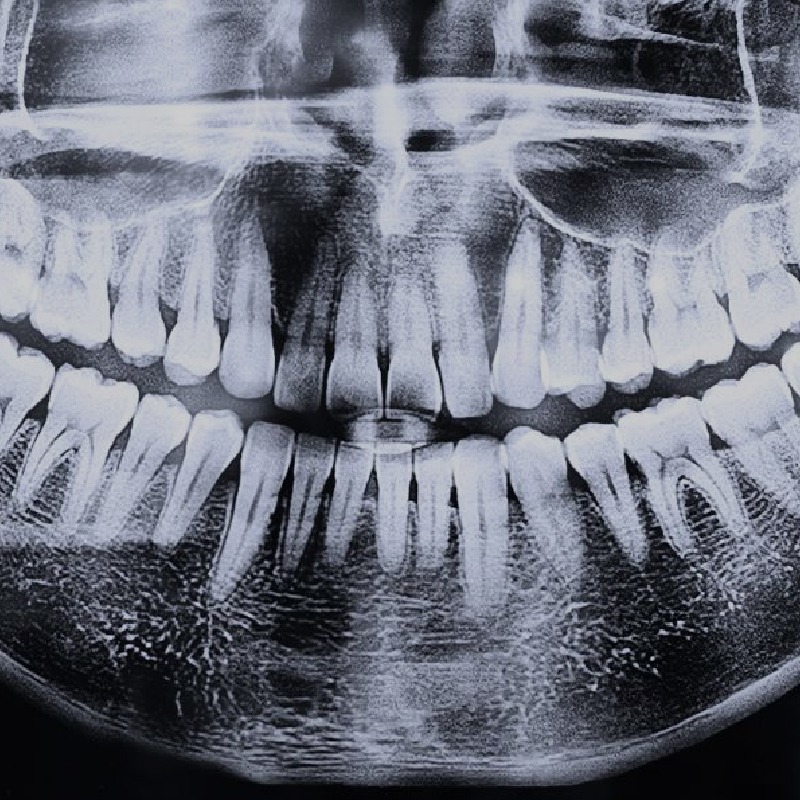

DIENTES FUERTES